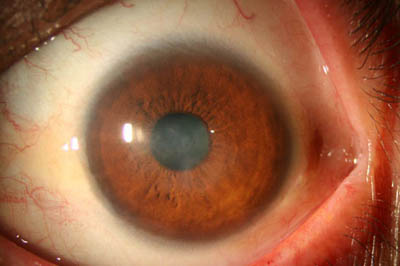

- Superficie corneal irregular y grisacea

- Opacidades granulares en parche

Superficie corneal irregular y grisácea

Opacidades granulares en parche

Opacidades superficiales satélites

Ulceración epitelial variante